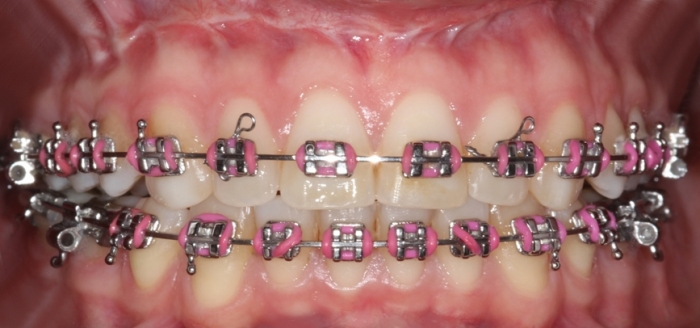

Mordida após a cirurgia